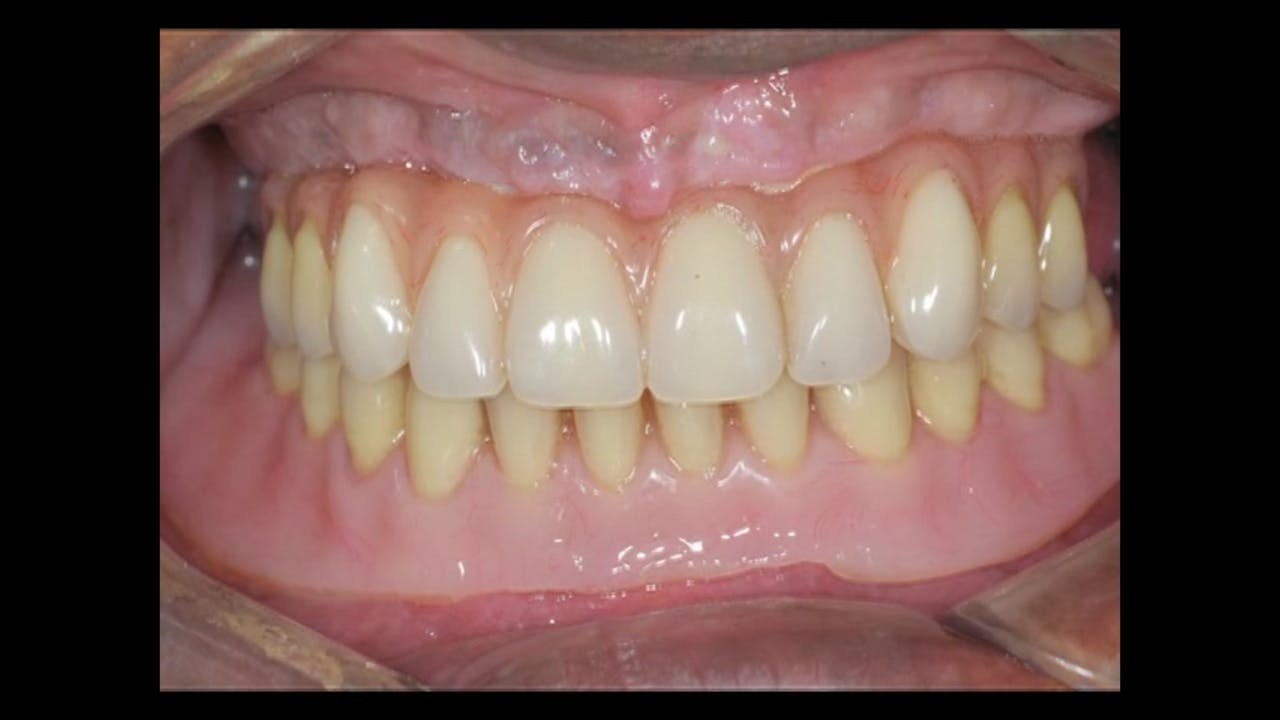

Before / After GIDE Dental Implant Center Gide Dental Reviews Gide dental institute, los angeles, california. 31,762 likes · 74 talking about this · 887 were. Find reviews, ratings, directions, business hours, and book appointments online. Dive deep (at your own pace) in a comprehensive online master class or residency with topics covering implant dentistry, esthetic dentistry,. • 550+ clinical videos on web and app • new dental videos added.. Gide Dental Reviews.

Before / After GIDE Dental Implant Center Gide Dental Reviews Premiere provider of online dental education. Learn from the world's most trusted faculty and advance your skills with gide. Find reviews, ratings, directions, business hours, and book appointments online. Clinical videos, expert interviews, live broadcasts over. Gide dental | 280 followers on linkedin. • 550+ clinical videos on web and app • new dental videos added. Dive deep (at your. Gide Dental Reviews.